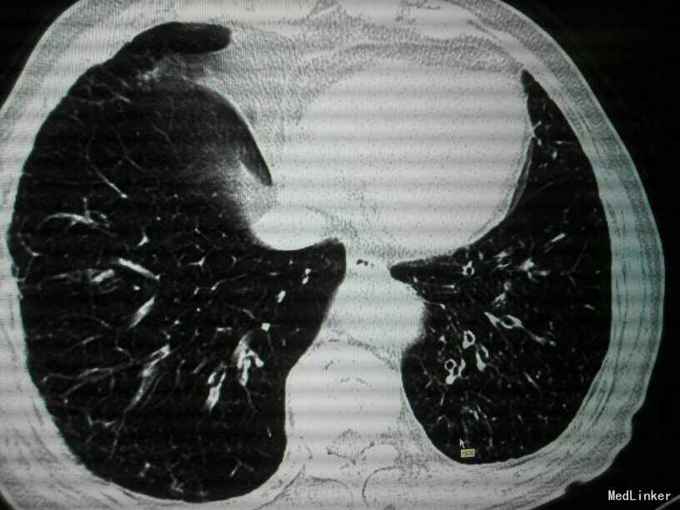

查体:唇指发绀,桶状胸,肋间隙增宽,双肺叩诊呈过清音,双肺呼吸音粗,可闻及散在干湿性啰音,未闻及明显湿性罗音,呼气延长,心腹阴性,双下肢轻度水肿。 辅助检查:入院后血气分析 PH 7.41 PCO2 43mmHg,PO2 73mmHg,BE 2.7mmol/L SO2:96%;心电图:室性早搏;胸片:符合慢支合并双肺炎症;肺CT示1.两肺多发支气管扩张并感染2.两肺间质纤维化,两侧胸膜增厚;心脏彩超:肺动脉压增高,肺动脉略宽;痰培养:肺炎克雷伯杆菌亚种;

诊断:慢阻肺急性发作;支气管扩张并感染;肺间质纤维化;慢性肺心病 治疗经过:抗炎:哌拉西林他唑巴坦;化痰:羧甲司坦口服液+盐酸氨溴索针;解痉平喘:多索茶碱,复方异丙托溴铵雾化溶液+布地奈德雾化混悬剂,雾化吸入;扩冠、减轻心脏负荷:硝酸甘油针;利尿:拖拉塞米针;3日后停硝酸甘油,改单硝酸异山梨酯缓释片口服,后患者出现胸闷、胸痛、气短症状加重,请心内科会诊后,给予呋塞米20㎎,隔日1次口服;螺内酯片20㎎,1日1次;替米沙坦片40㎎ 1日1次;美托洛尔6.25㎎;氯化钾缓释片 0.5g,1日2次;并给予抗血小板聚集、调脂、稳定斑块等治疗;治疗10天后,患者受凉后出现畏寒、发热,侧体温38.1℃,停哌拉西林他唑巴坦,改为盐酸莫西沙星针0.4g,1日1次,其余治疗同前;治疗3天后患者体温恢复正常,偶有咳嗽,咳少量白色黏痰,症状好转,出院。